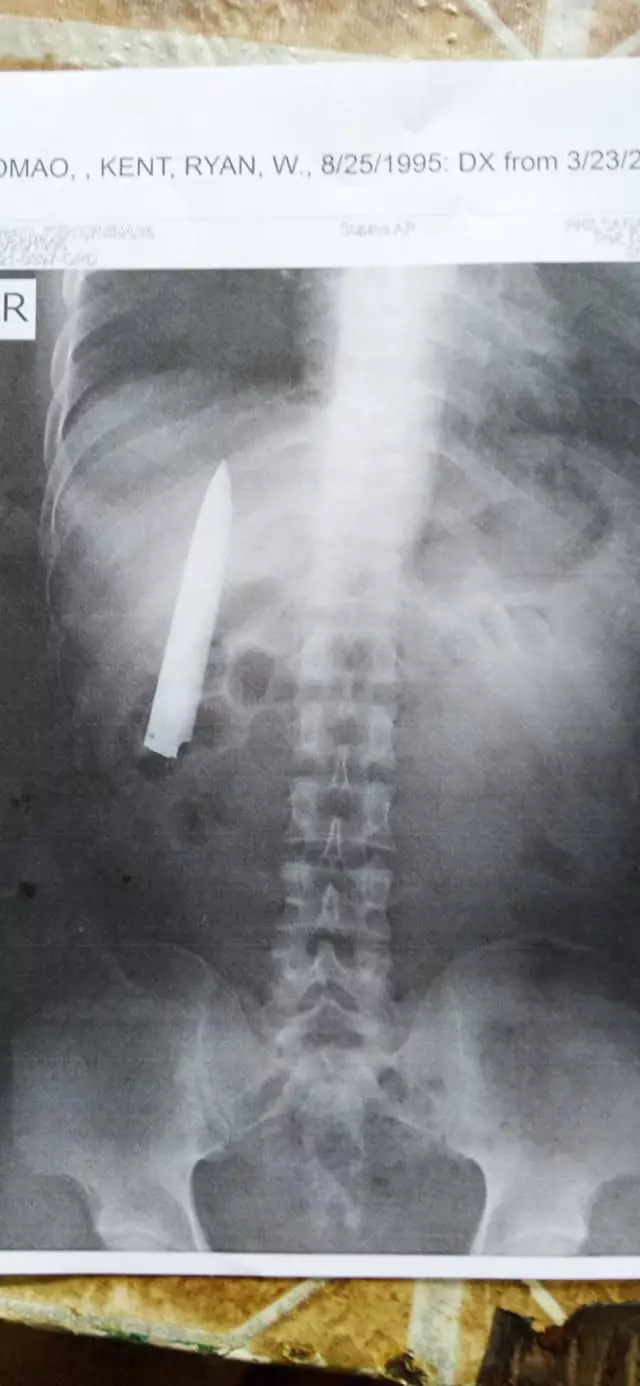

A Filipino man was unaware he had a knife stuck on his chest for more than a year. Kent Ryan Tomao, 36, was attacked and stabbed while walking home from work in Kidapawan City, the Philippines, in January last year. Bungling medics treated him but instead of removing the knife, they simply sewed up the wound leaving the broken-off blade stuck in his chest. Shockingly, Kent had the weapon lodged next to his rib cage just inches from piercing his lungs for more than a year before it was discovered during a health check for a new job on Tuesday (March 23). Kent is now furious that the doctors missed the four-inch-long knife blade and is demanding they remove it properly so he can start work as a miner, as his new employers believe it is not safe for him to go down pits with the knife inside him. He said: 'The doctors did not check my wounds properly last year so I believe they are partly at fault about what happened. They should fix this.' The worker claimed that the doctors only stitched his wounds to stop them from bleeding at the hospital. He was given painkillers and sent home. Fourteen months later Kent was hired at a mining company in nearby province Agusan del Sur and he was set to start next month. The company required a pre-employment medical test but an x-ray examination found the knife pointing upwards and stuck in his rib cage. Kent said his chest was sometimes painful during the cold weather but everything was tolerable and he never believed there was a serious problem. He said: ‘I always wondered why I felt pain in my chest when the weather was cold. But I had no idea there is a knife in my chest. 'The pain was never bad enough to even go to see a doctor. I just waited for the pain to pass. Now I'm relieved that I know the real problem.' The worker will have to undergo an operation to remove the knife before he can start working but he said he doesn�,Image: 600944390, License: Rights-managed, Restrictions: , Model Release: no

A Filipino man was unaware he had a knife stuck on his chest for more than a year. Kent Ryan Tomao, 36, was attacked and stabbed while walking home from work in Kidapawan City, the Philippines, in January last year. Bungling medics treated him but instead of removing the knife, they simply sewed up the wound leaving the broken-off blade stuck in his chest. Shockingly, Kent had the weapon lodged next to his rib cage just inches from piercing his lungs for more than a year before it was discovered during a health check for a new job on Tuesday (March 23). Kent is now furious that the doctors missed the four-inch-long knife blade and is demanding they remove it properly so he can start work as a miner, as his new employers believe it is not safe for him to go down pits with the knife inside him. He said: 'The doctors did not check my wounds properly last year so I believe they are partly at fault about what happened. They should fix this.' The worker claimed that the doctors only stitched his wounds to stop them from bleeding at the hospital. He was given painkillers and sent home. Fourteen months later Kent was hired at a mining company in nearby province Agusan del Sur and he was set to start next month. The company required a pre-employment medical test but an x-ray examination found the knife pointing upwards and stuck in his rib cage. Kent said his chest was sometimes painful during the cold weather but everything was tolerable and he never believed there was a serious problem. He said: ‘I always wondered why I felt pain in my chest when the weather was cold. But I had no idea there is a knife in my chest. 'The pain was never bad enough to even go to see a doctor. I just waited for the pain to pass. Now I'm relieved that I know the real problem.' The worker will have to undergo an operation to remove the knife before he can start working but he said he doesn�,Image: 600944403, License: Rights-managed, Restrictions: , Model Release: no

A Filipino man was unaware he had a knife stuck on his chest for more than a year. Kent Ryan Tomao, 36, was attacked and stabbed while walking home from work in Kidapawan City, the Philippines, in January last year. Bungling medics treated him but instead of removing the knife, they simply sewed up the wound leaving the broken-off blade stuck in his chest. Shockingly, Kent had the weapon lodged next to his rib cage just inches from piercing his lungs for more than a year before it was discovered during a health check for a new job on Tuesday (March 23). Kent is now furious that the doctors missed the four-inch-long knife blade and is demanding they remove it properly so he can start work as a miner, as his new employers believe it is not safe for him to go down pits with the knife inside him. He said: 'The doctors did not check my wounds properly last year so I believe they are partly at fault about what happened. They should fix this.' The worker claimed that the doctors only stitched his wounds to stop them from bleeding at the hospital. He was given painkillers and sent home. Fourteen months later Kent was hired at a mining company in nearby province Agusan del Sur and he was set to start next month. The company required a pre-employment medical test but an x-ray examination found the knife pointing upwards and stuck in his rib cage. Kent said his chest was sometimes painful during the cold weather but everything was tolerable and he never believed there was a serious problem. He said: ‘I always wondered why I felt pain in my chest when the weather was cold. But I had no idea there is a knife in my chest. 'The pain was never bad enough to even go to see a doctor. I just waited for the pain to pass. Now I'm relieved that I know the real problem.' The worker will have to undergo an operation to remove the knife before he can start working but he said he doesn�,Image: 600944414, License: Rights-managed, Restrictions: , Model Release: no